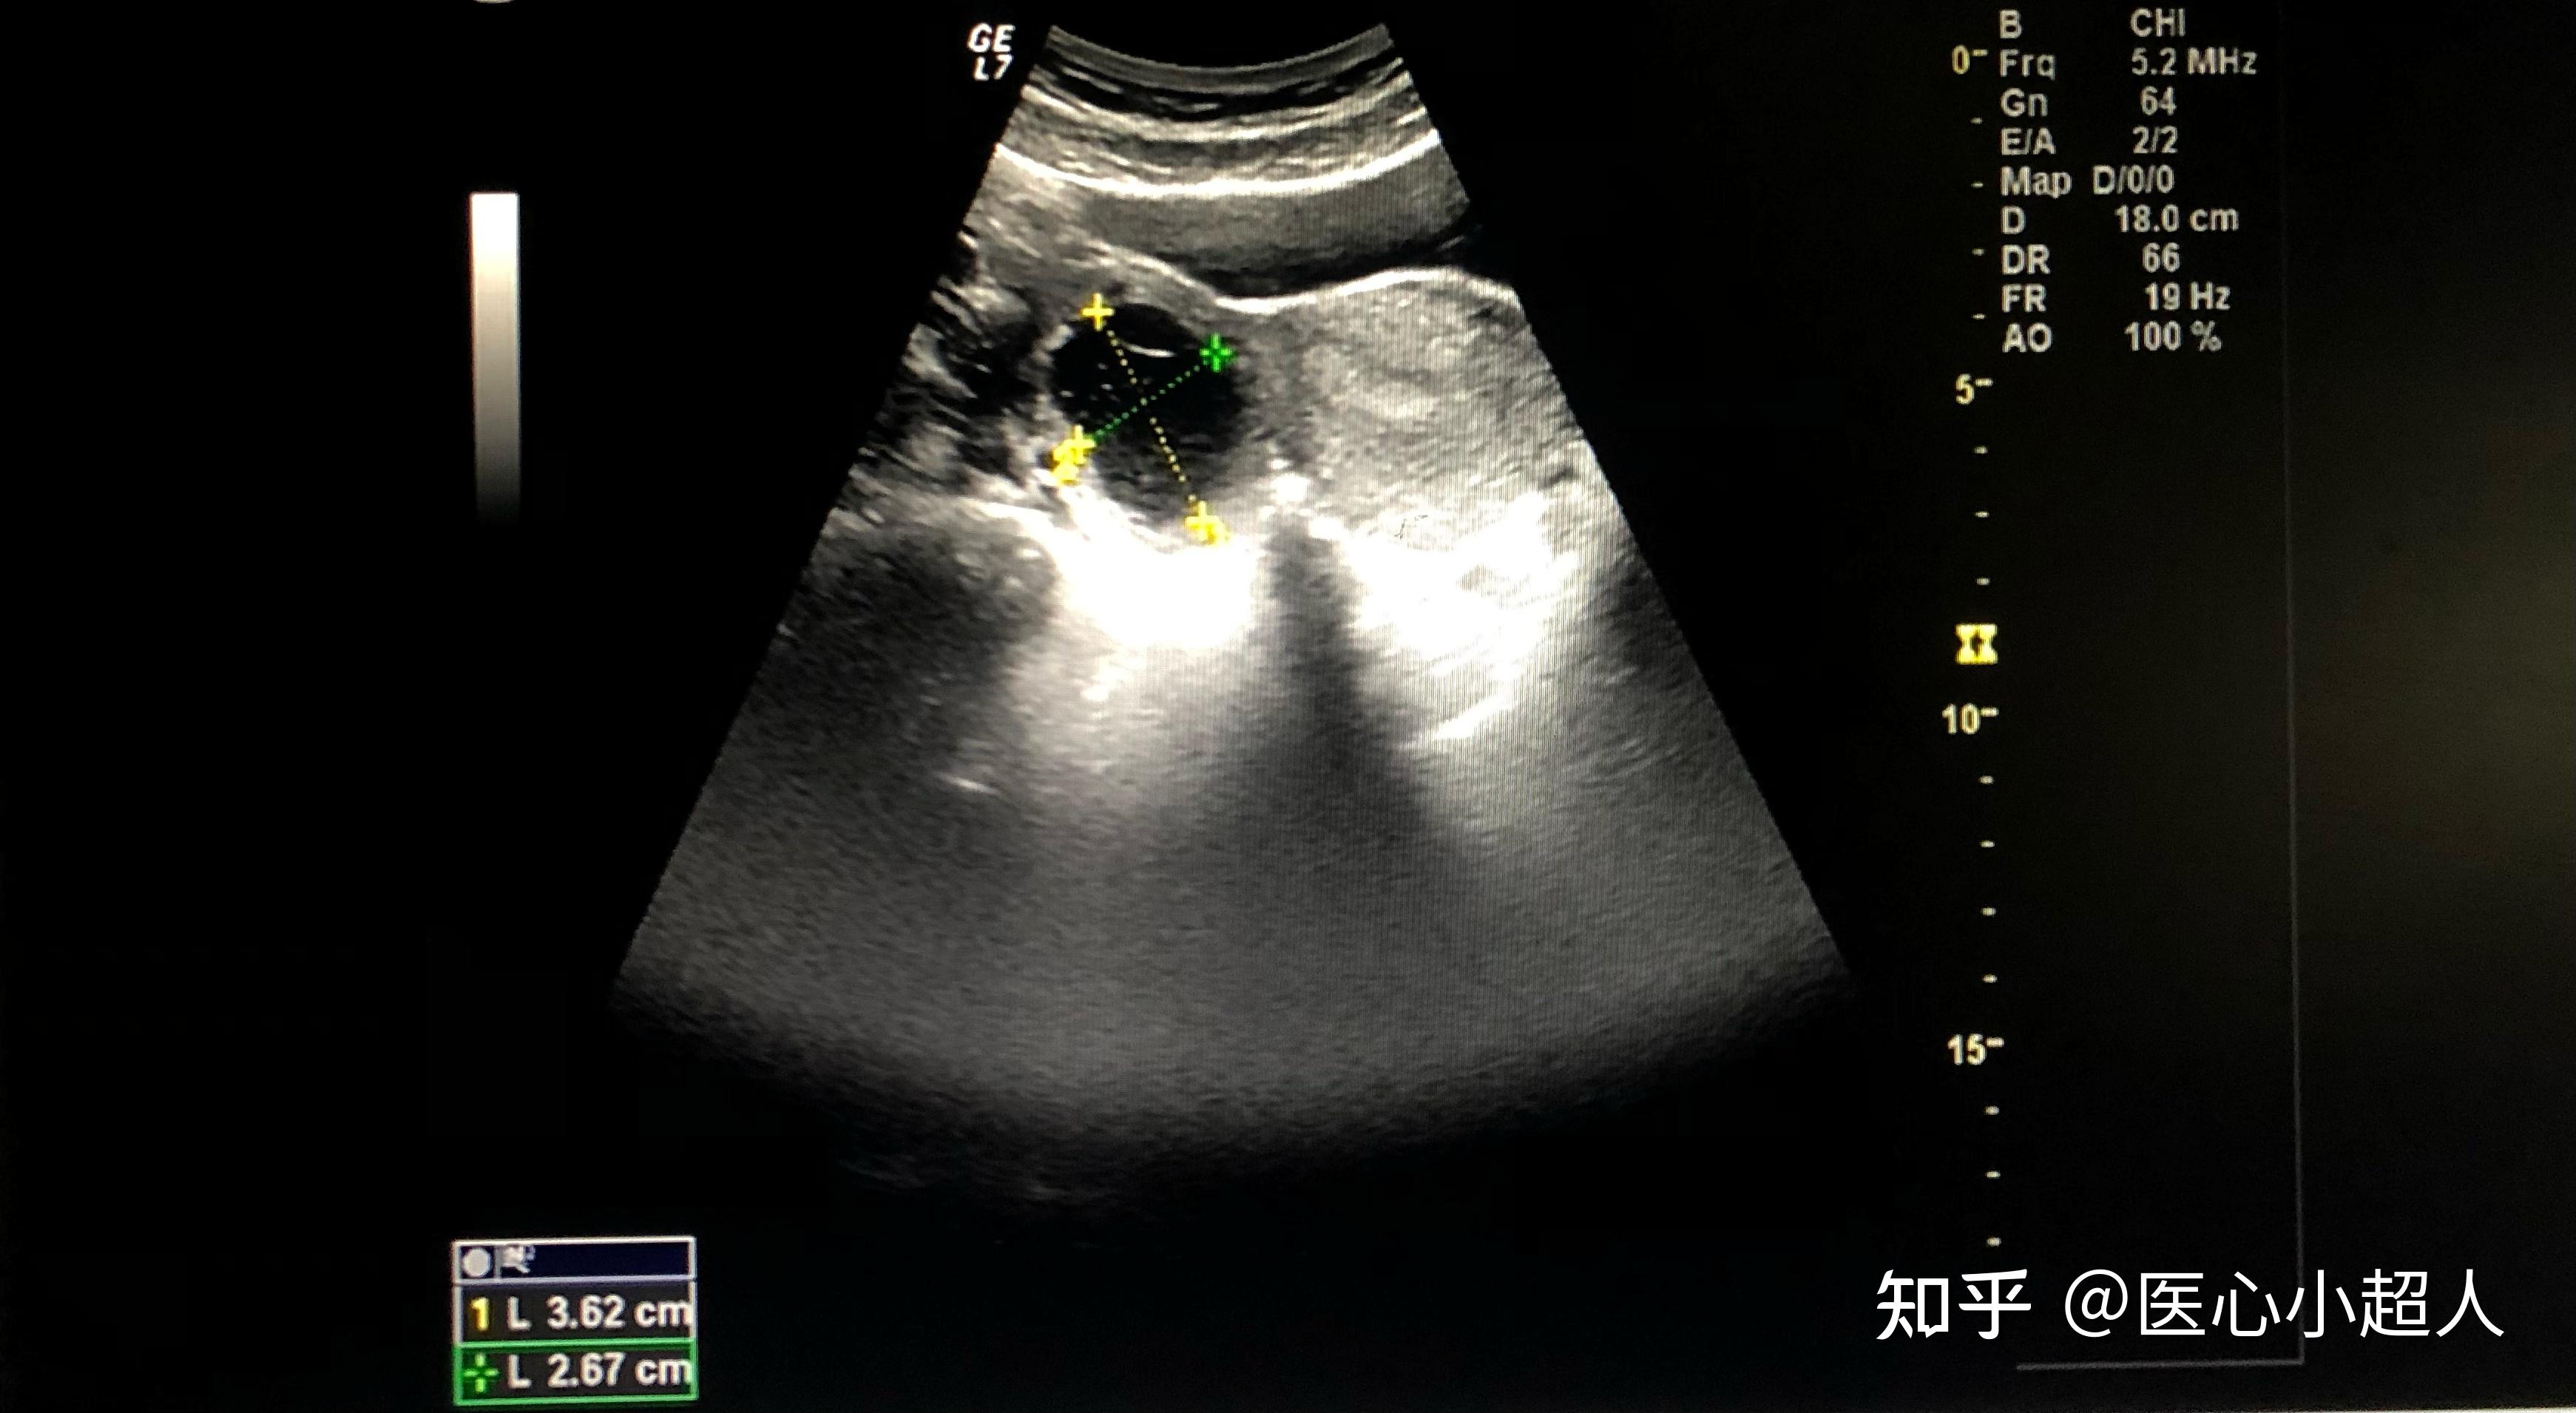

备孕期间查出卵巢肿瘤2个医生说要手术

图片尺寸960x1280